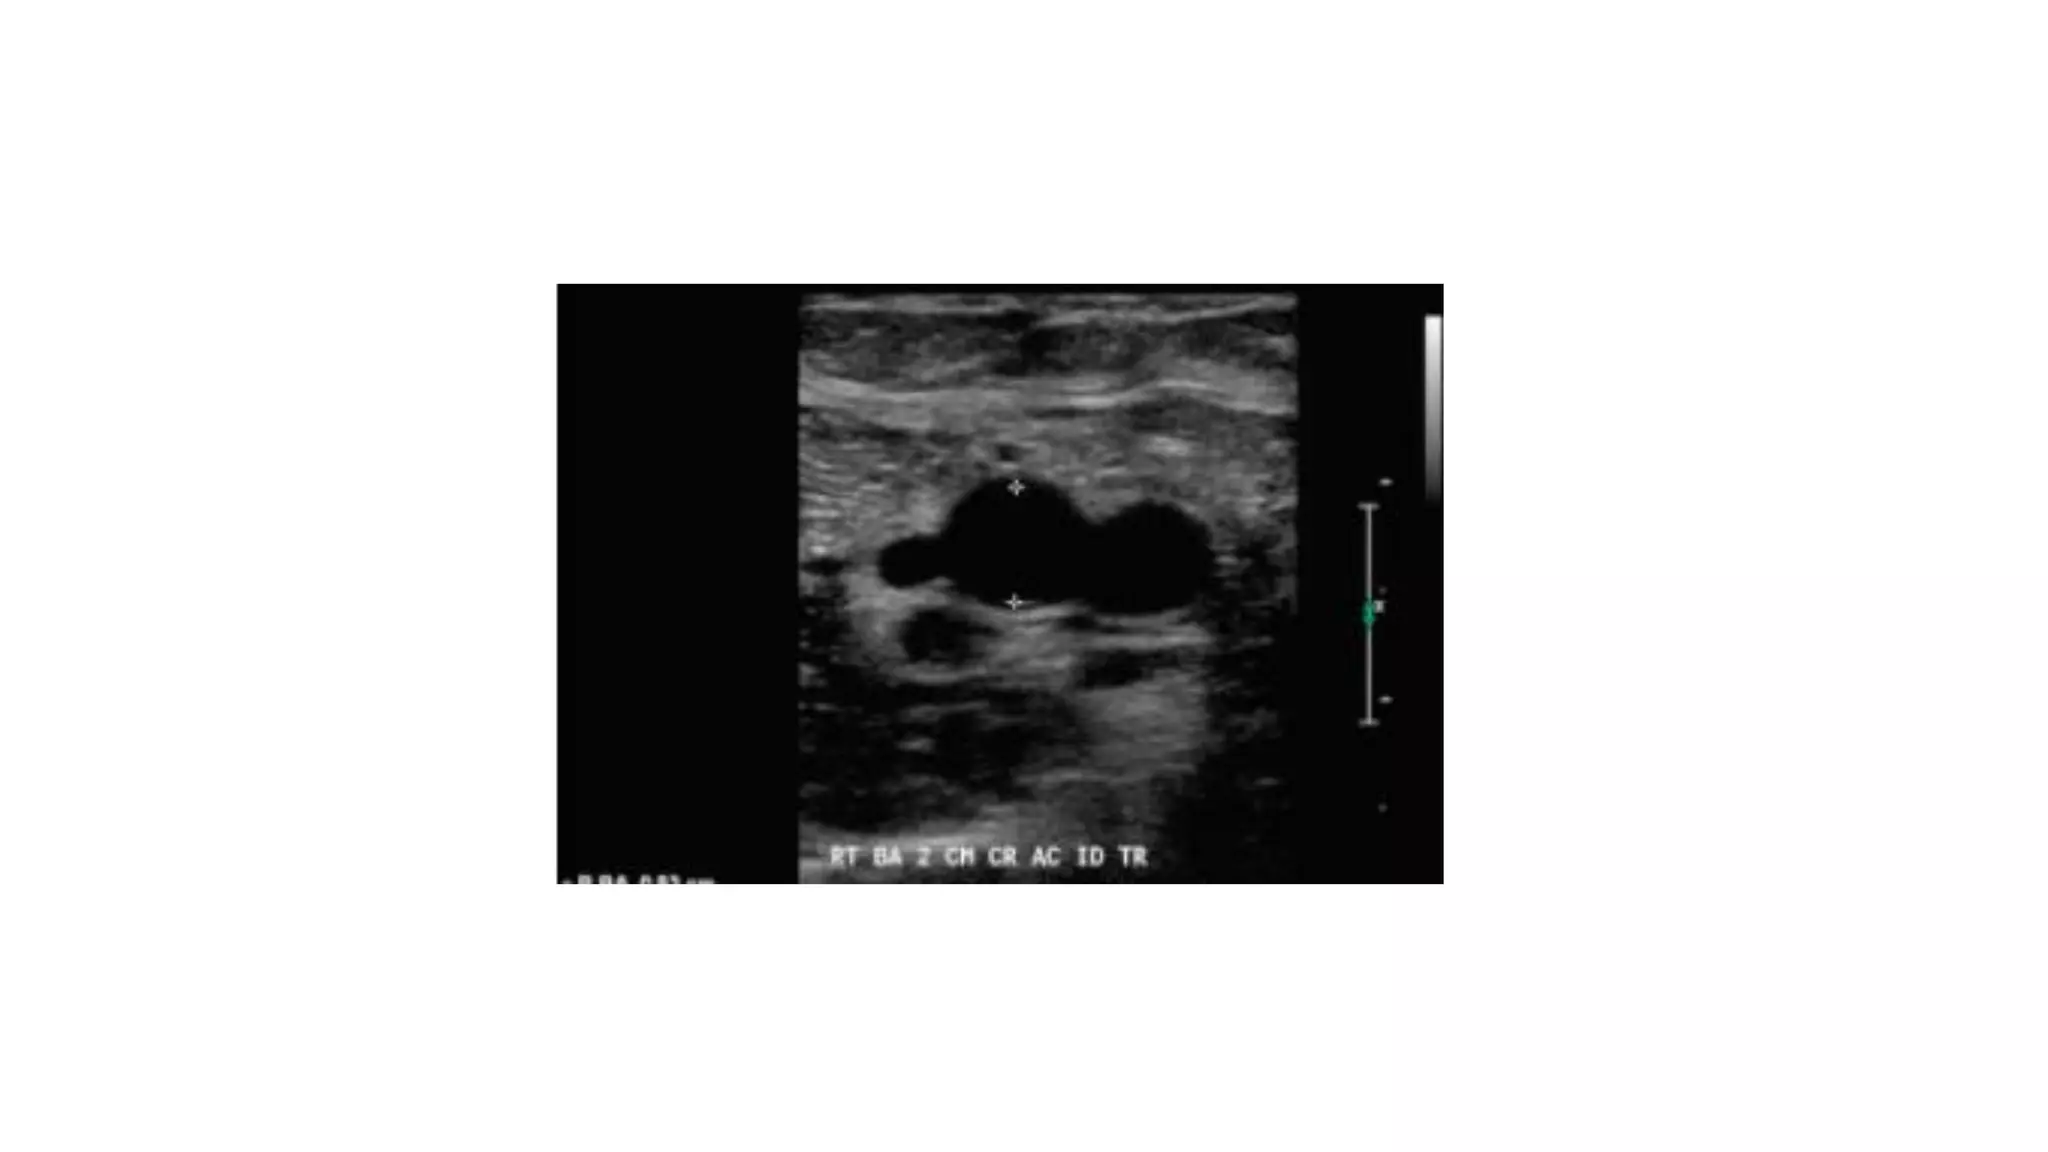

Ultrasound vascular mapping uses ultrasound to examine arteries and veins in the arms before dialysis access placement. It assesses vessel diameter, wall characteristics, blood flow, compressibility, and identifies the best vessels. The mapping examines arteries for internal diameter and wall appearance, uses Doppler to evaluate blood flow, and may check for calcification. It also assesses superficial arm veins for caliber, depth, wall appearance, distensibility, course, patency, and presence of collaterals to identify the best vessel options for dialysis access. A vein mapping worksheet is used to report the ultrasound findings.